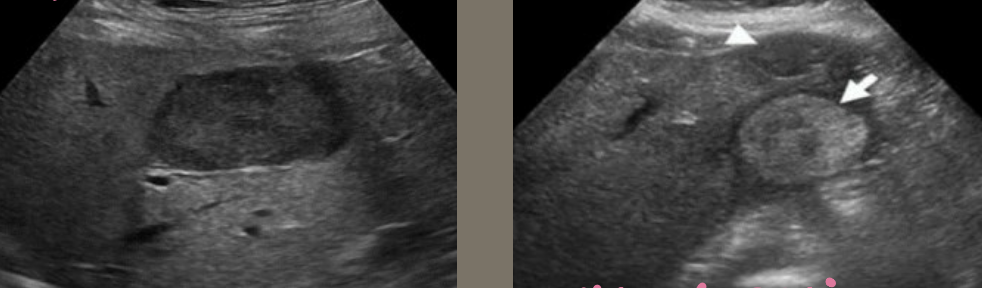

Metastatic Disease (METS) → most common form of neoplastic involvement of the liver

2D US: single or multiple solid lesions, varying sizes, can have bullseye appearance, echogenic, or hypoechoic, enlarged liver, can cause pseudo nodularity

color doppler: hypo to hypervascular

DDX: HCC, hemangioma, lymphoma